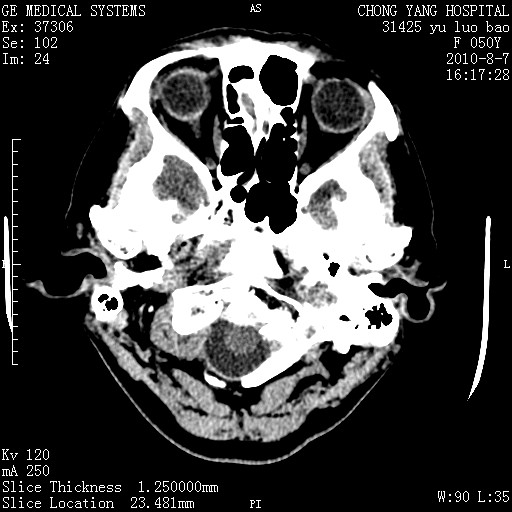

标题: CT28285:听力下降一年,头昏。 [打印本页]

标题: CT28285:听力下降一年,头昏。

右侧桥小脑角区占位--听神经瘤,建议增强或mri检查。

右侧桥小脑角去等密度占位,右侧内听道扩大、骨质吸收,考虑:右侧听神经瘤,建议增强检查。

右侧内听道扩大、骨质吸收,中脑受压左移,考虑:右侧听神经瘤,建议增强检查。支持!

右侧桥小脑角区等密度占位,内耳道扩大,听神经瘤